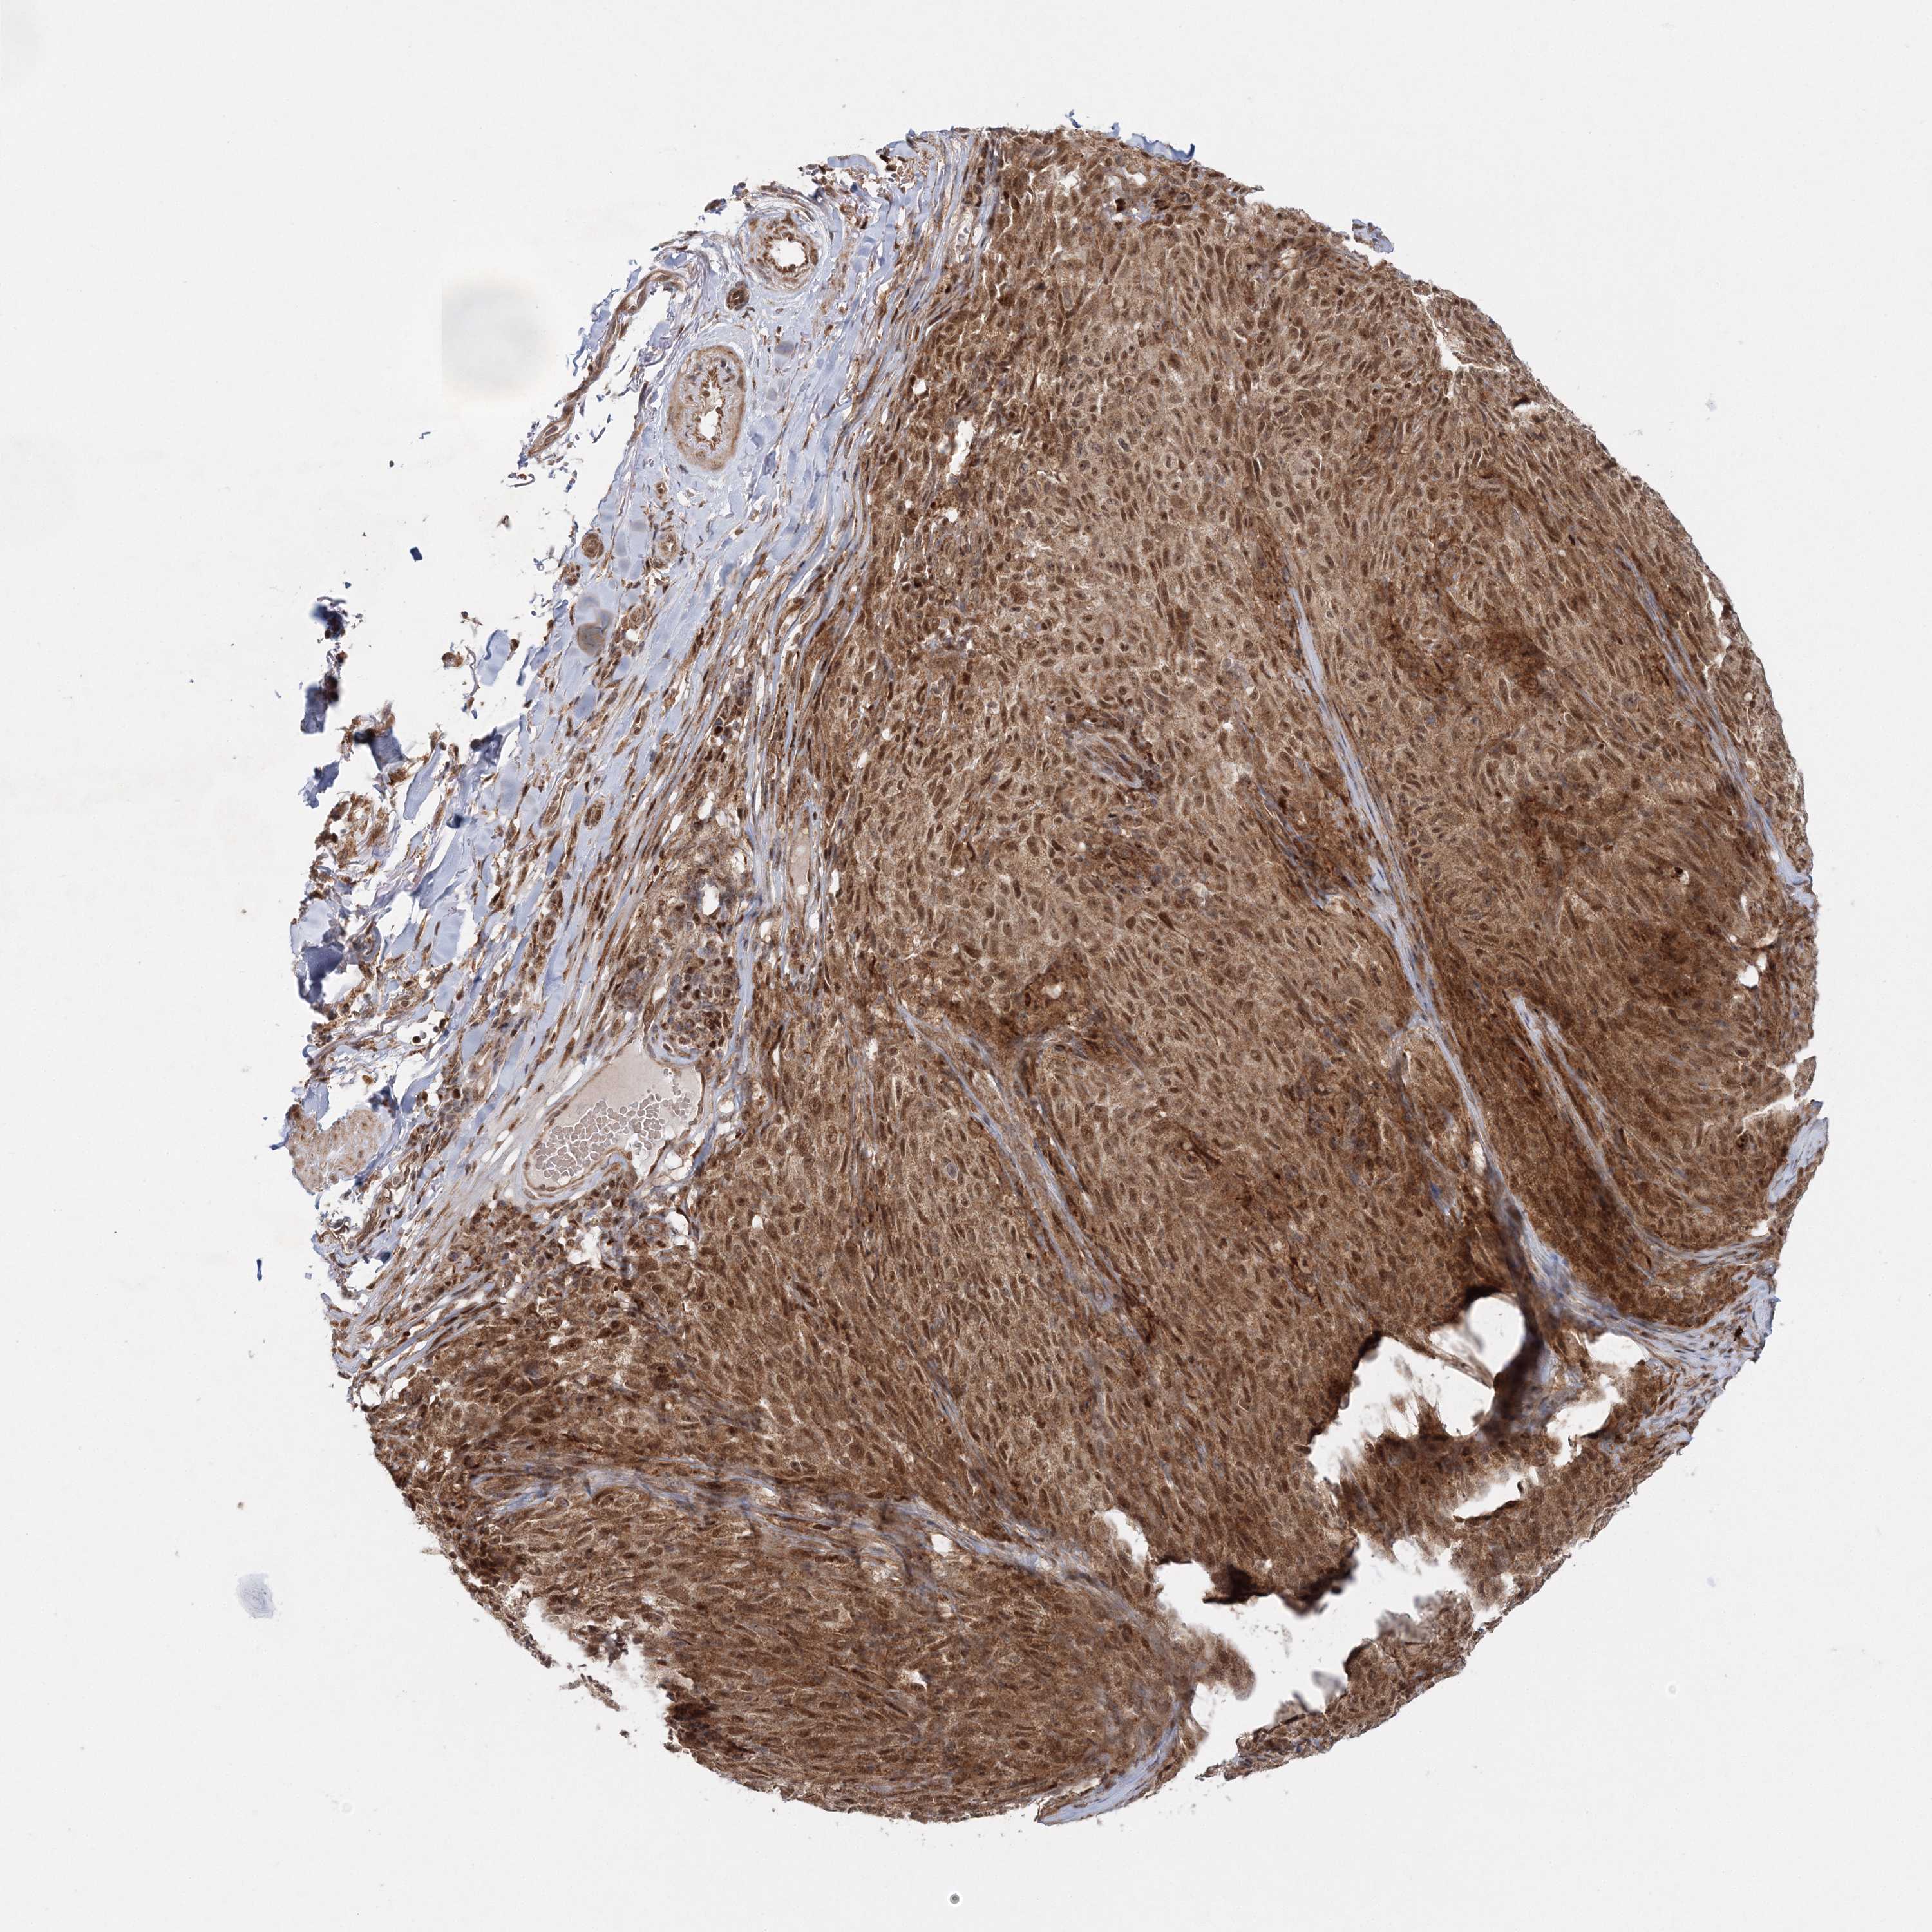

MELANOMA - Protein expressioni

A mouse-over function shows sample information and annotation data. Click on an image to view it in a full screen mode. Samples can be filtered based on level of antibody staining by selecting one or several of the following categories: high, medium, low and not detected. The assay and annotation is described here.

Note that samples used for immunohistochemistry by the Human Protein Atlas do not correspond to samples in the TCGA dataset.

Antibody stainingi

Antibody staining in the annotated cell types in the current human tissue is reported as not detected, low, medium, or high, based on conventional immunohistochemistry profiling in selected tissues. This score is based on the combination of the staining intensity and fraction of stained cells.

Each image is clickable and will lead to virtual microscopy that enables deeper exploration of all samples and also displays staining intensity scores, fraction scores and subcellular localization as well as patient and tissue information for each sample.

Antibody HPA037726

Staining

High

Medium

Low

Not detected

Intensity

Strong

Moderate

Weak

Negative

Quantity

>75%

75%-25%

<25%

None

Location

Nuclear

Cytoplasmic/membranous

Cytoplasmic/membranous,nuclear

Malignant melanoma, NOS

Malignant melanoma, Metastatic site